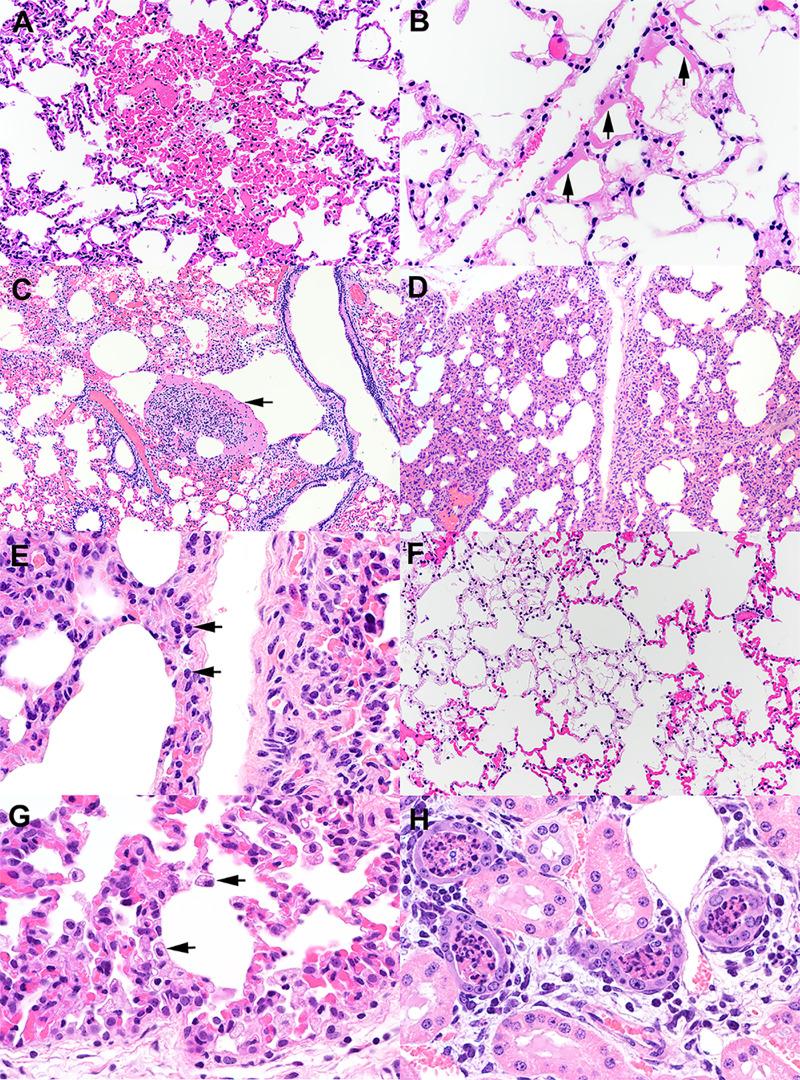

白尾鹿()对严重急性呼吸综合征冠状病毒2(SARS-CoV-2)的易感性。

Susceptibility of white-tailed deer () to SARS-CoV-2.

The origin of severe acute respiratory syndrome coronavirus 2 (SARS-CoV-2), the virus causing the global coronavirus disease 19 (COVID-19) pandemic, remains a mystery. Current evidence suggests a likely spillover into humans from an animal reservoir. Understanding the host range and identifying animal species that are susceptible to SARS-CoV-2 infection may help to elucidate the origin of the virus and the mechanisms underlying cross-species transmission to humans. Here we demonstrated that white-tailed deer (), an animal species in which the angiotensin converting enzyme 2 (ACE2) - the SARS-CoV-2 receptor - shares a high degree of similarity to humans, are highly susceptible to infection. Intranasal inoculation of deer fawns with SARS-CoV-2 resulted in established subclinical viral infection and shedding of infectious virus in nasal secretions. Notably, infected animals transmitted the virus to non-inoculated contact deer. Viral RNA was detected in multiple tissues 21 days post-inoculation (pi). All inoculated and indirect contact animals seroconverted and developed neutralizing antibodies as early as day 7 pi. The work provides important insights into the animal host range of SARS-CoV-2 and identifies white-tailed deer as a susceptible wild animal species to the virus.Given the presumed zoonotic origin of SARS-CoV-2, the human-animal-environment interface of COVID-19 pandemic is an area of great scientific and public- and animal-health interest. Identification of animal species that are susceptible to infection by SARS-CoV-2 may help to elucidate the potential origin of the virus, identify potential reservoirs or intermediate hosts, and define the mechanisms underlying cross-species transmission to humans. Additionally, it may also provide information and help to prevent potential reverse zoonosis that could lead to the establishment of a new wildlife hosts. Our data show that upon intranasal inoculation, white-tailed deer became subclinically infected and shed infectious SARS-CoV-2 in nasal secretions and feces. Importantly, indirect contact animals were infected and shed infectious virus, indicating efficient SARS-CoV-2 transmission from inoculated animals. These findings support the inclusion of wild cervid species in investigations conducted to assess potential reservoirs or sources of SARS-CoV-2 of infection.

摘要